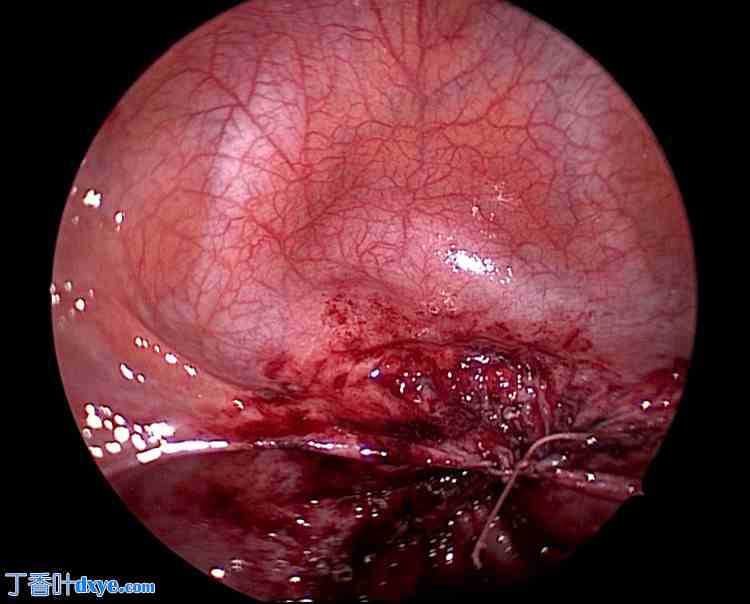

对阴道残端的脆弱组织进行清创。清创后,用生理盐水充分冲洗周围区域。随后,在腹腔镜引导下经阴道缝合伤口(图 7-9)。首先,在腹腔镜的引导下,经阴道缝合阴道壁。然后,从腹腔侧缝合腹膜,形成双层缝合。

图 7. 阴道壁缝合后。